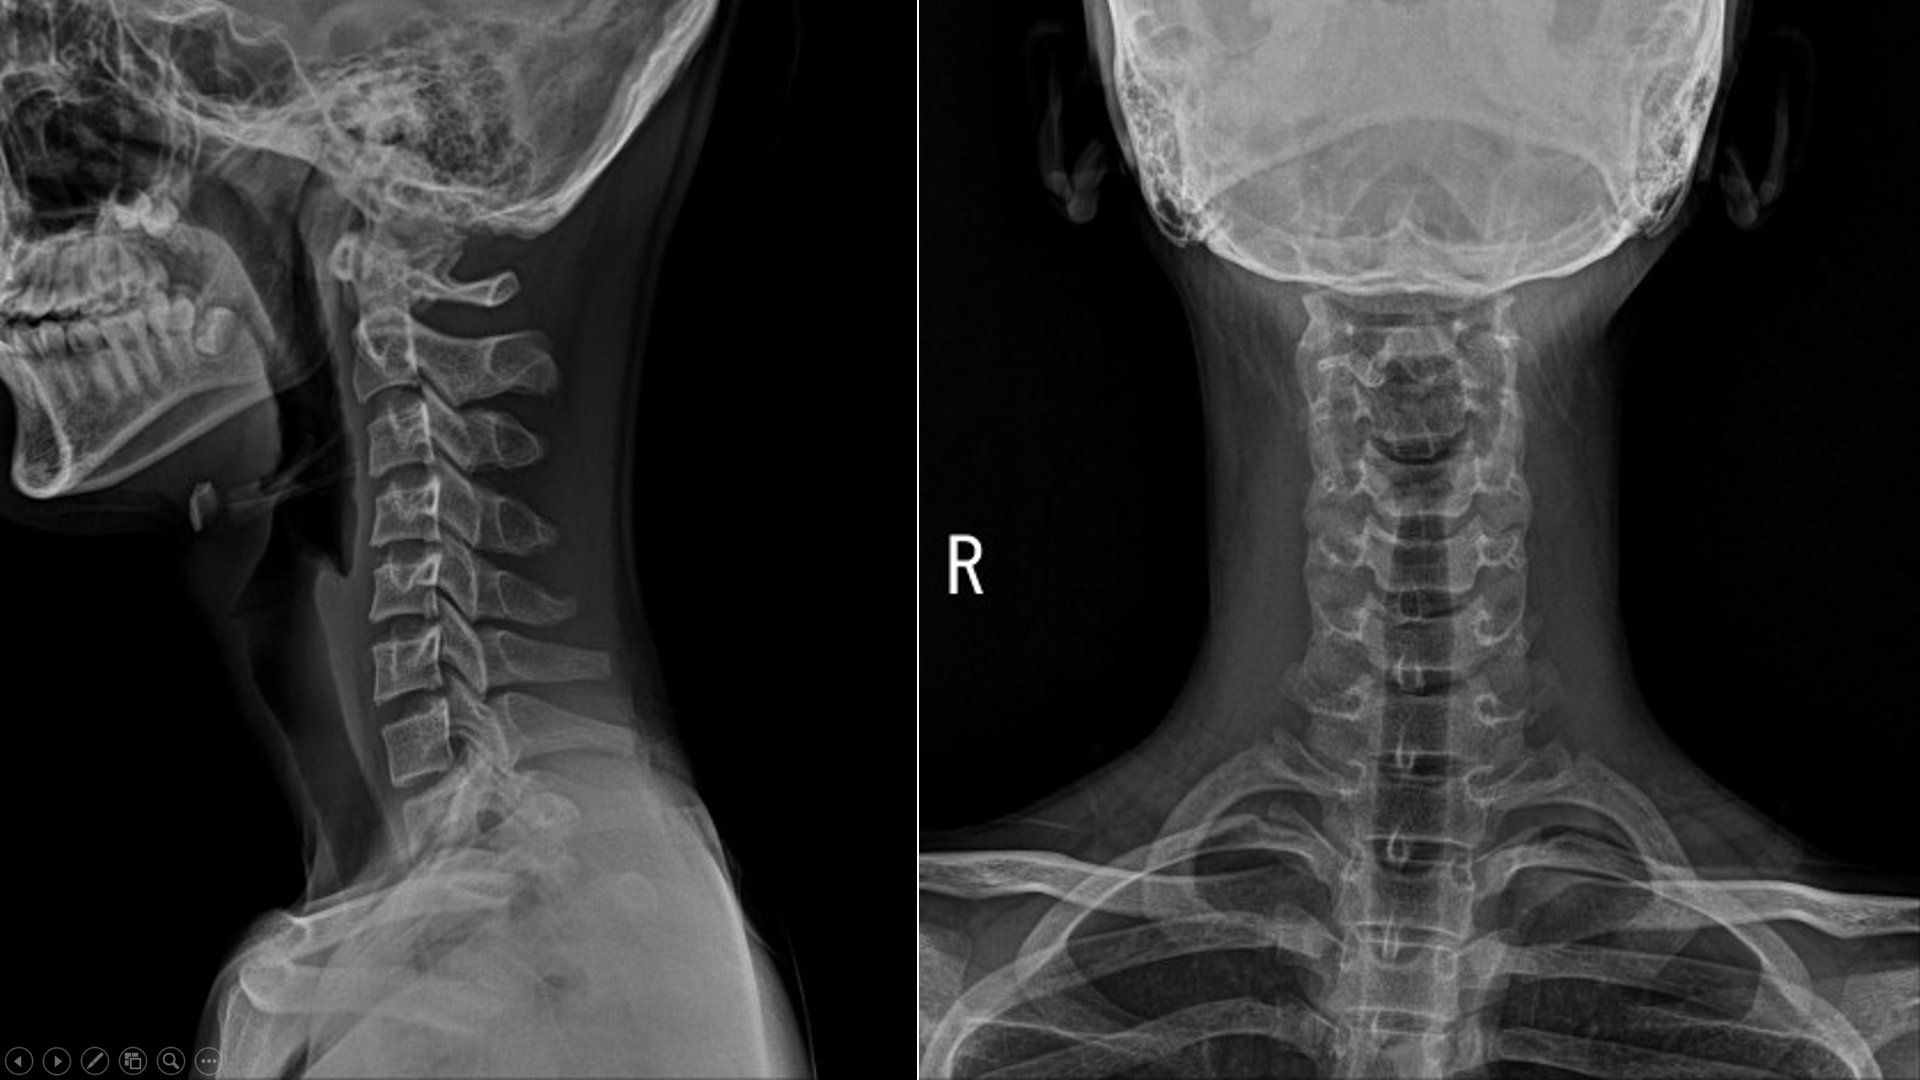

14세 남환

오늘 자고 일어나서 목이 아파 돌리기 힘들다 해서 어머니와 내원

x ray촬영을 해봄

일자목이....

"일단 목이 아파서 일자목으로 촬영될 가능성이 있지만, 일자목으로 보입니다."